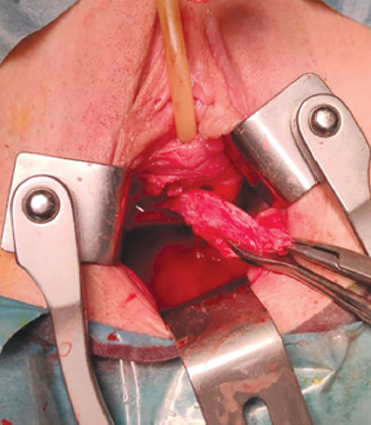

Surgery course. An incision was made along the anterior wall of the vagina after hydropreparation (Fig. 2). A paraurethral cyst with a diameter of about 6 cm was bluntly and sharply separated (Fig. 3). Its walls were excised (Fig. 4). The bladder was filled up to 250 cm; there was no urine leakage into the wound. The cyst bed (Fig. 5) was sutured with interrupted sutures (Vicryl 3–0). A Bülau drain was installed in the wound to the cyst bed, the incision of the vagina was sutured, and hemostasis was performed. A tampon was placed in the vagina. The urinary bladder was drained with a Foley catheter 18 Ch.

Fig. 3.Exposure of the paraurethral cyst walls

Рис. 3.Выделение стенок парауретральной кисты

Fig. 4.Exposure of the paraurethral cyst walls

Рис. 4.Иссечение стенок парауретральной кисты